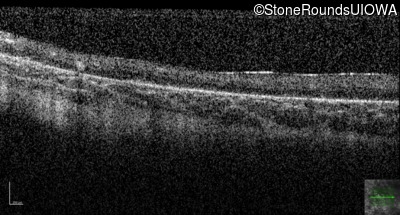

Optical Coherence Tomography - Right - Hand Motion 1' sc

Exemplar / OCT Stack